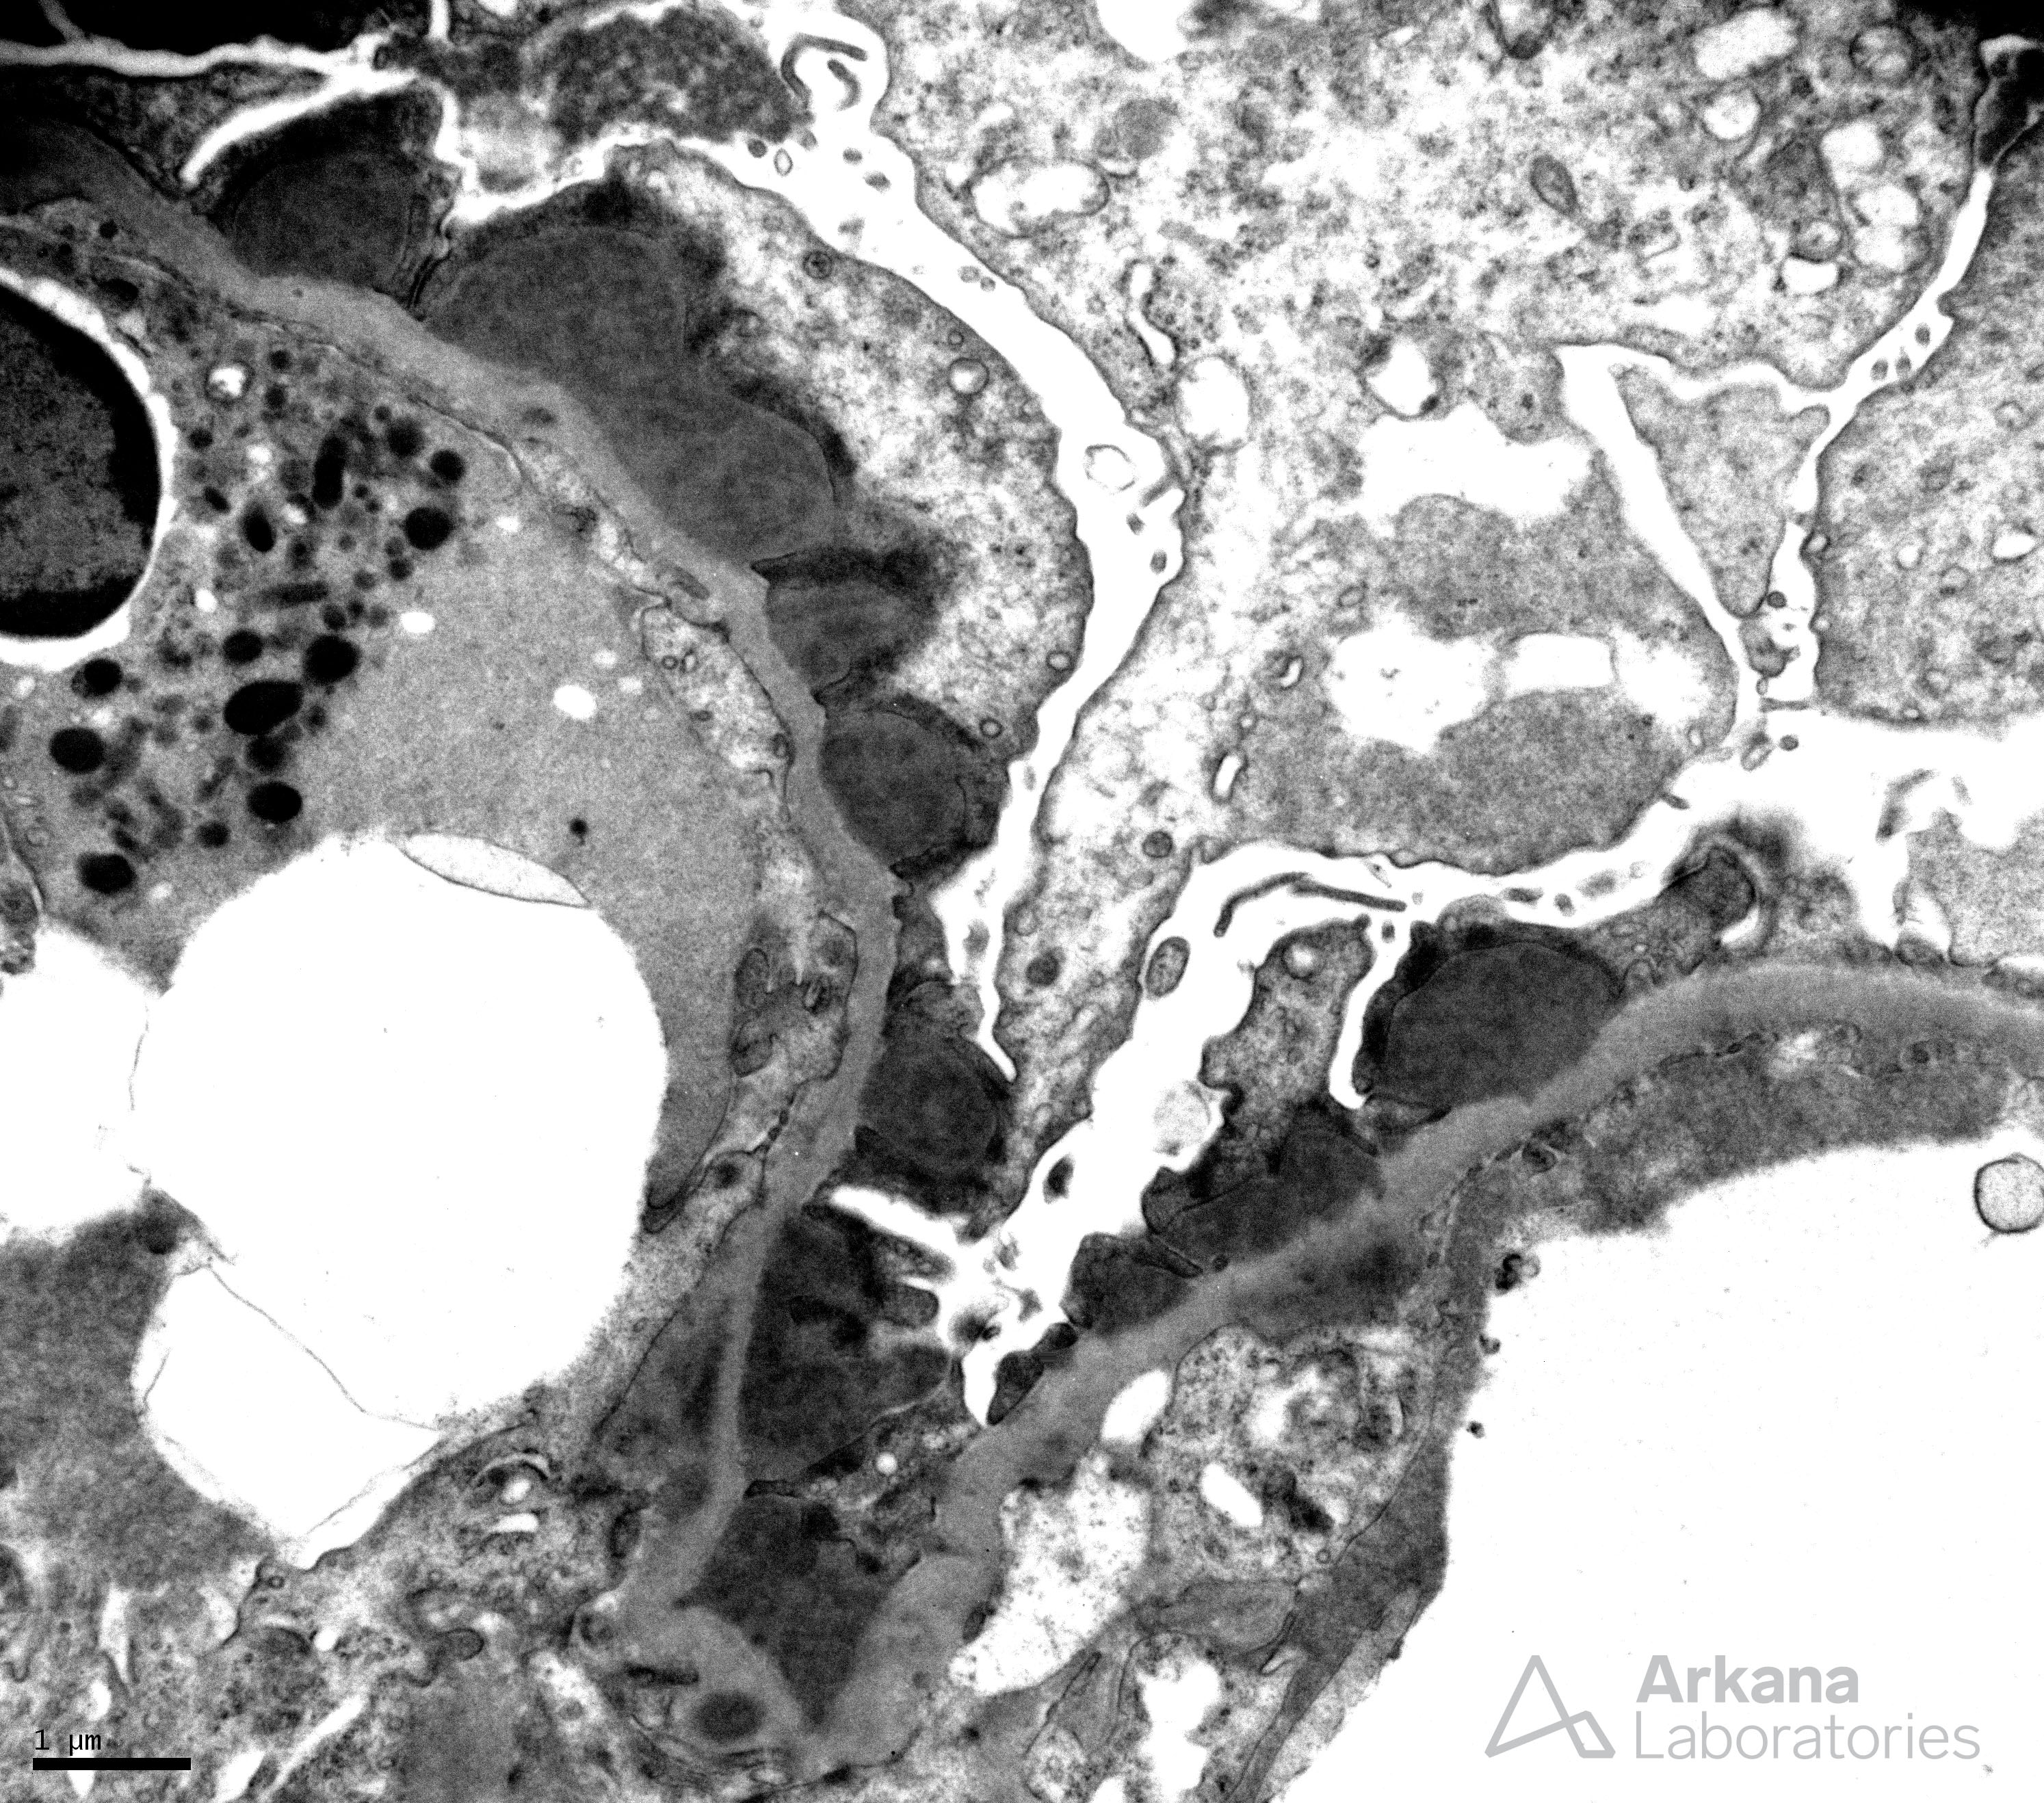

Infection-Associated Subepithelial Hump Formation